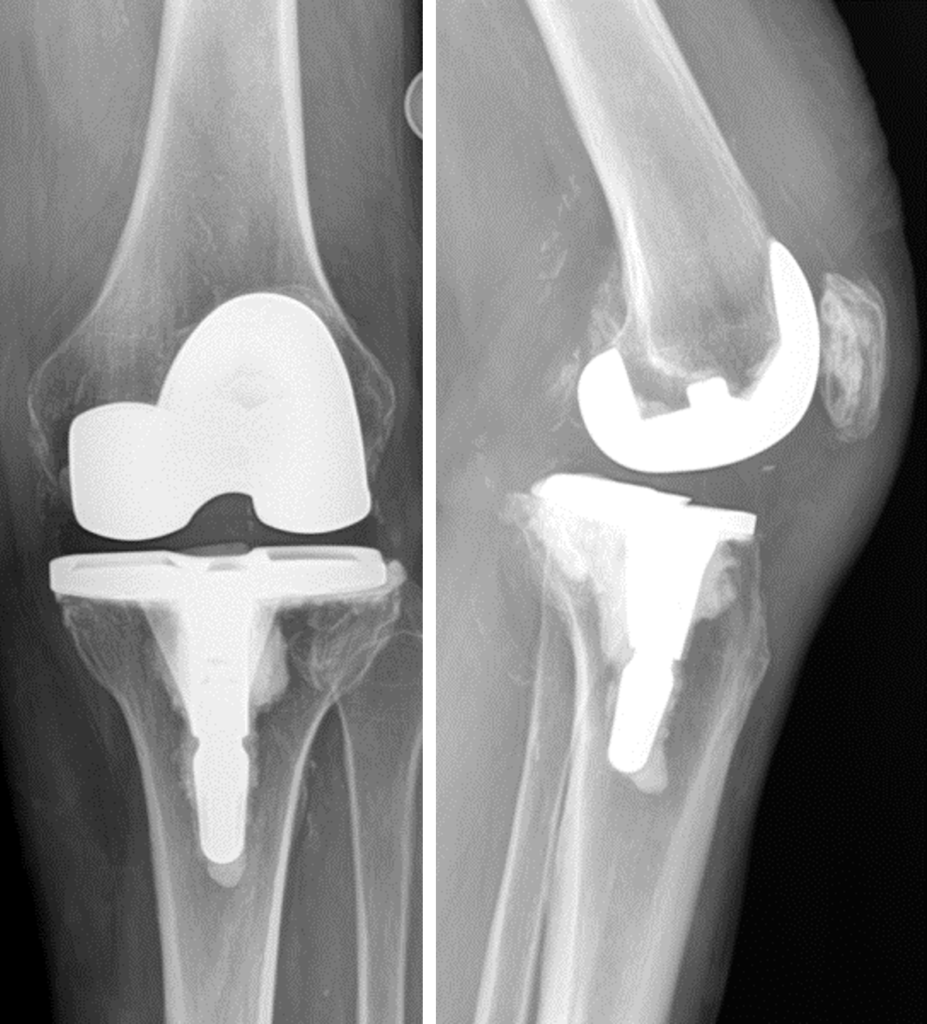

Knee replacement is a surgery whereby the surfaces of the knee joint are replaced by artificial surfaces (commonly metal and plastic parts). The arthritic surfaces of the femur (thigh bone) and tibia (shin bone) at the knee are removed and replaced with metal load bearing surfaces. A plastic liner that will fit onto the new metal tibial surface and articulate with the new artificial metal surface on the femur is inserted as well (figure 2). A plastic (or metal and plastic) piece may or may not be used to resurface the patella (knee cap) depending upon how much arthritis is present in this part of the joint.